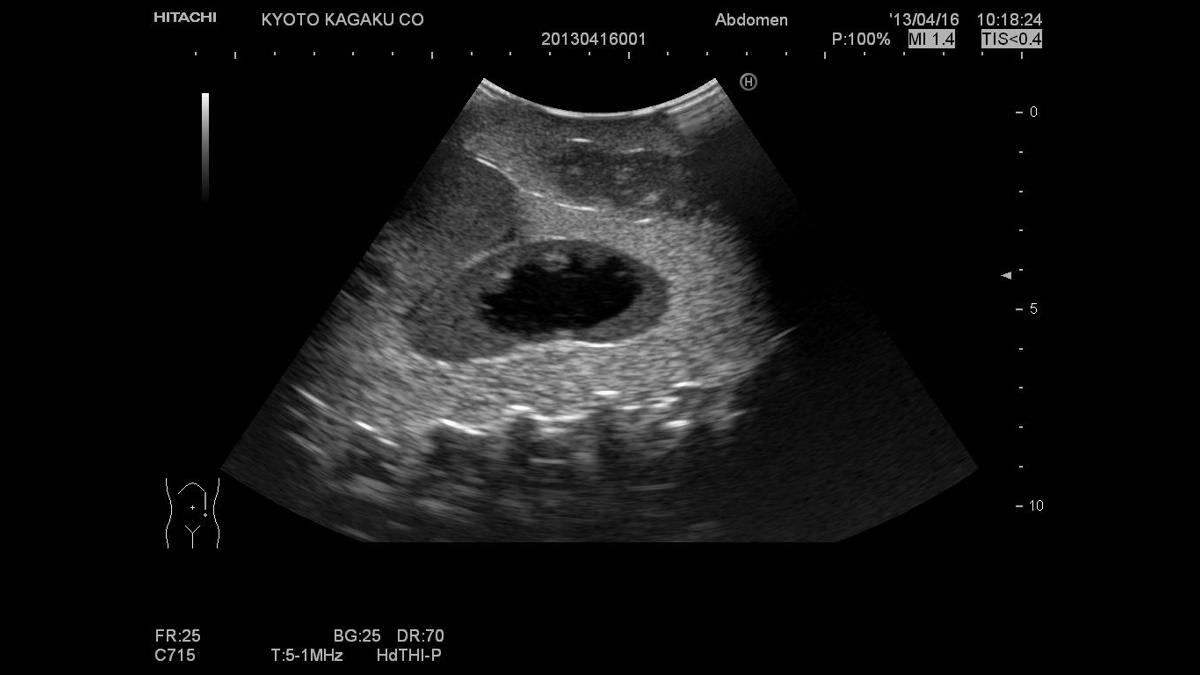

The Paediatric FAST/Acute Abdomen Phantom facilitates the practice of hands-on training using ultrasound to examine young patients. Using FAST procedures, trainees are able to identify internal haemorrhage at the perihepatic, perisplenic, pelvis, and pericardium area, whilst the ultrasound capabilities of the module allow for bowel intussusception, appendicitis and biliary dilatation recognition.

Sonography for acute paediatric patient, helping to identify bowel intussusception, appendicitis and biliary dilatation